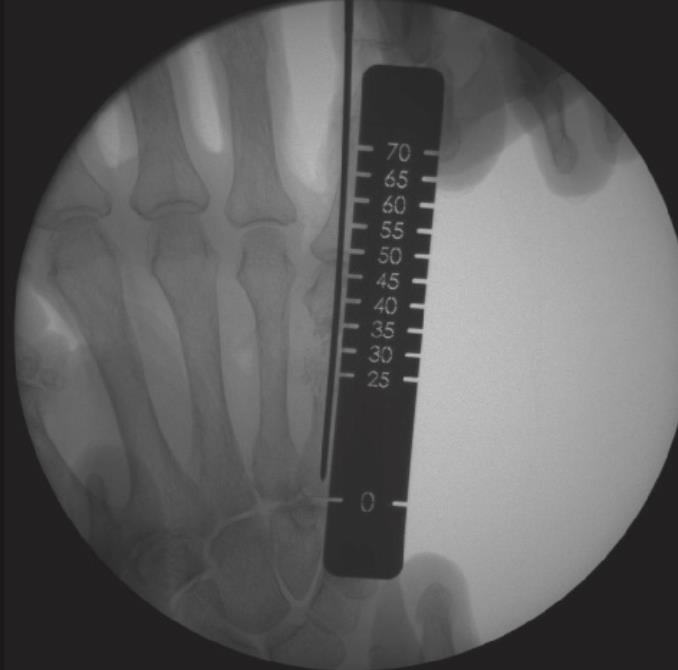

• determine nail length with a measurement ruler or depth gauge and subtract 10mm from the length reading

• available lengths

• 40mm

• 45mm

• 50mm

• 55mm

• 60mm

• 65mm

• 70mm